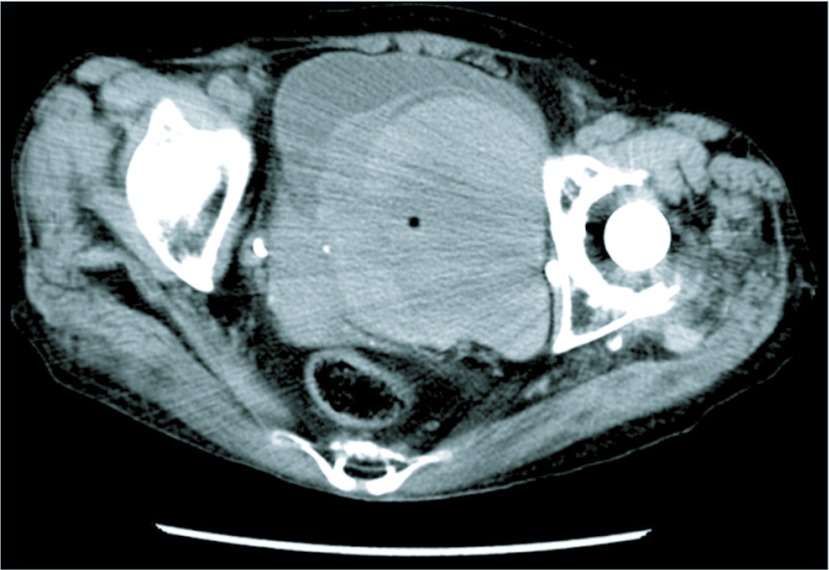

Fig. 2.

A plain CT showed a profuse amount of high density shadow suggesting a hematoma filling most of the bladder.